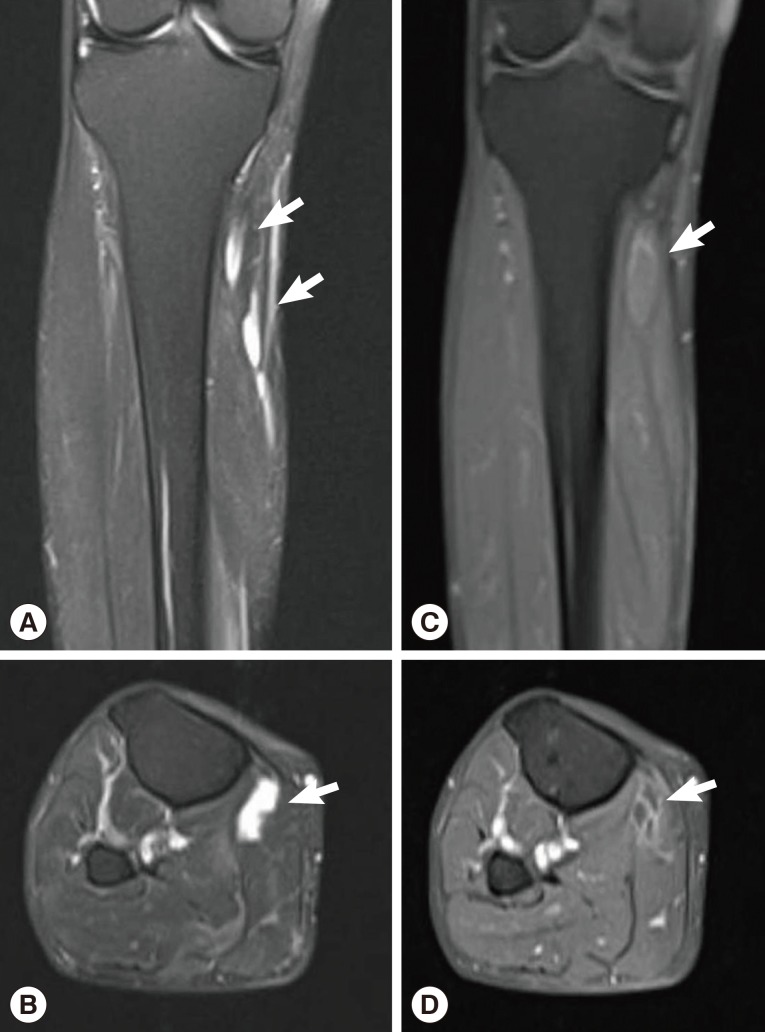

Sixteen months after the operation, the patient revisited our hospital because of pain and paresthesia of the right thigh and a mass at the posterior aspect of the right distal thigh. Physical examination revealed generalized pain and a tingling sensation on the right thigh and multiple soft, mobile, non-tender masses at the posterior aspect of the right proximal tibia. MRI revealed a 1.8 cm-sized, well-circumscribed round mass arising at the right distal sciatic nerve. The lesion showed heterogeneous high signal intensity on T2-weighted images and intermediate signal intensity on T1-weighted images with a target sign or a fascicular sign, and a benign neurogenic tumor, such as a schwannoma or neurofibroma, was suspected (Fig. 4). Multifocal tubular and cystic lesions were also detected around the mass, showing high signal intensity on T2-weighted images and low signal intensity on T1-weighted images (Fig. 5).

Fig. 5

MRI showing multifocal tubular and cystic lesions of high signal intensity on T2-weighted images (arrows) (A, B) and low signal intensity on T1-weighted images (arrows) (C, D) around the mass.

Fig. 5 MRI showing multifocal tubular and cystic lesions of high signal intensity on T2-weighted images (arrows) (A, B) and low signal intensity on T1-weighted images (arrows) (C, D) around the mass.